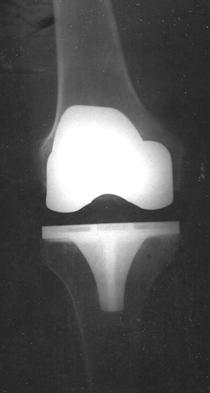

Больной получает антибиотики для снижения риска развития инфекции. Производится разрез для получения доступа к внутренним поверхностям сустава. Затем удаляются участки хряща и костной ткани с нижней поверхности бедренной кости и верхней поверхности большеберцовой кости. После этого производится имплантация искусственного сустава, сделанного обычно из металла и пластика (см. рис. 2).

Тип имплантата, метод операции и локализация разреза зависят от индивидуальных предпочтений пациента и хирурга, выполняющего операцию. Все протезы коленного сустава состоят из бедренного компонента, большеберцового и надколенникового компонентов. Существует множество вариантов протеза от разных производителей. Большинство из них служит не менее 10 лет. Искусственный сустав действует дольше у пожилых, менее физически активных пациентов и у больных ревматоидным артритом (по сравнению с больными остеоартритом).

После проведения имплантации производится контрольный рентгеновский снимок колена (см. рис. 3,4).

Он позволяет хирургу подтвердить и документировать правильное положение сустава и служит для сравнения с последующими снимками.

Полная замена коленного сустава это распространенная хирургическая процедура, которая может помочь в случаях, когда неоперативные методы лечения (использование наколенников или ортопедических стелек и медикаментозное лечение) не помогают. Операция включает в себя замену всех трех отделов коленного сустава (см. рис. 1) протезом с тем, чтобы уменьшить боль и улучшить функционирование сустава. Большинство кандидатов на операцию страдают от болей в суставе из за артрита. При подготовке к замене коленного сустава пациент должен пройти обследование, включающее опрос, физикальное обследование, рентген, лабораторные анализы, а также обсудить с врачом все выгоды и возможные осложнения операции и получить информацию об альтернативных методах лечения. Операция проводится под анестезией для временного обездвиживания и снятия боли. Хирург производит разрез для доступа к полости коленного сустава и затем удаляет часть хряща и костной ткани с нижней поверхности бедренной кости и верхней поверхности большеберцовой кости. Далее производится вживление искусственного сустава, сделанного из металла и пластмасс. После операции пациент получает лекарства для предотвращения инфекции и для обезболивания. Также принимаются меры для предотвращения тромбообразования – препараты разжижающие кровь и сдавливающие устройства для ног или эластичные чулки. Некоторым пациентам предложат использование устройства для продолжительного пассивного движения – механизм, который приподнимает и медленно движет прооперированную ногу. После операции необходимо работать в тесном контакте с физиотерапевтом для укрепления мышечной силы и возобновления нормального объема движений в коленном суставе. Пациент может вернуться к нормальной деятельности в течение трех – шести недель после операции , после завершения программы реабилитации, может заниматься видами спорта с небольшой нагрузкой на коленный сустав (ходьба, плавание, езда на велосипеде). Послеоперационные осложнения возникают редко и, в основном, могут быть предотвращены с помощью тщательного послеоперационного ухода.